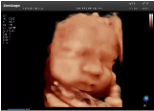

4容積探頭

積探頭是在二維圖像的基礎(chǔ)上,將連續(xù)采集的空間分布位置,經(jīng)過計算機(jī)重建算法,從而獲得完整的空間形態(tài)。

適用于:胎兒面部、脊柱和肢體等。

優(yōu)勢特點:快速獲取、掃查連續(xù)均勻、解剖結(jié)構(gòu)顯示為容積數(shù)據(jù)、準(zhǔn)確進(jìn)行容積測量。